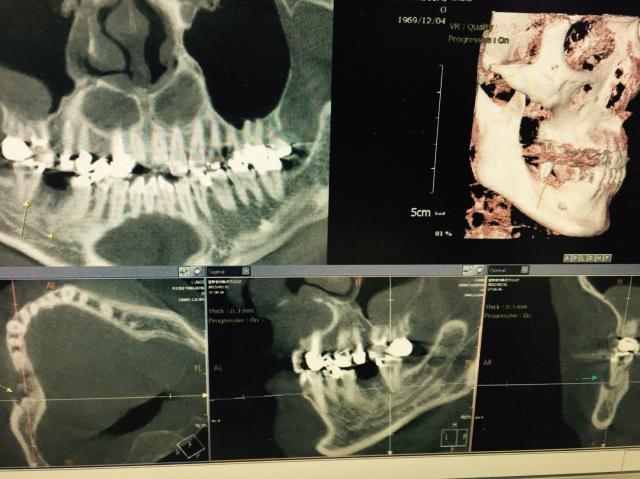

2015年 04月 11日 ( 土 ) インプラント症例

エムドゲインで骨や歯周組織を再生